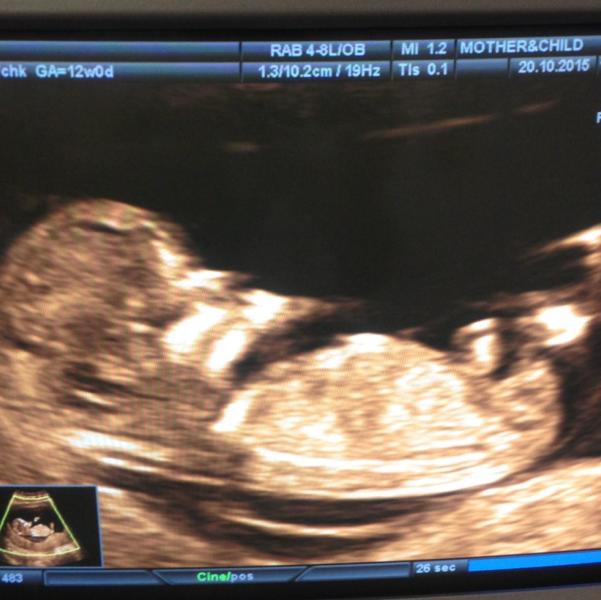

Первое узи))Была у Томашевой))все очень быстро ,но по теме))мужа пустили,сфоткать разрешила)))

Прелесть!) мне первое узи больше всего понравилось, потому что все тельце сразу видно, прям человек человечище!)